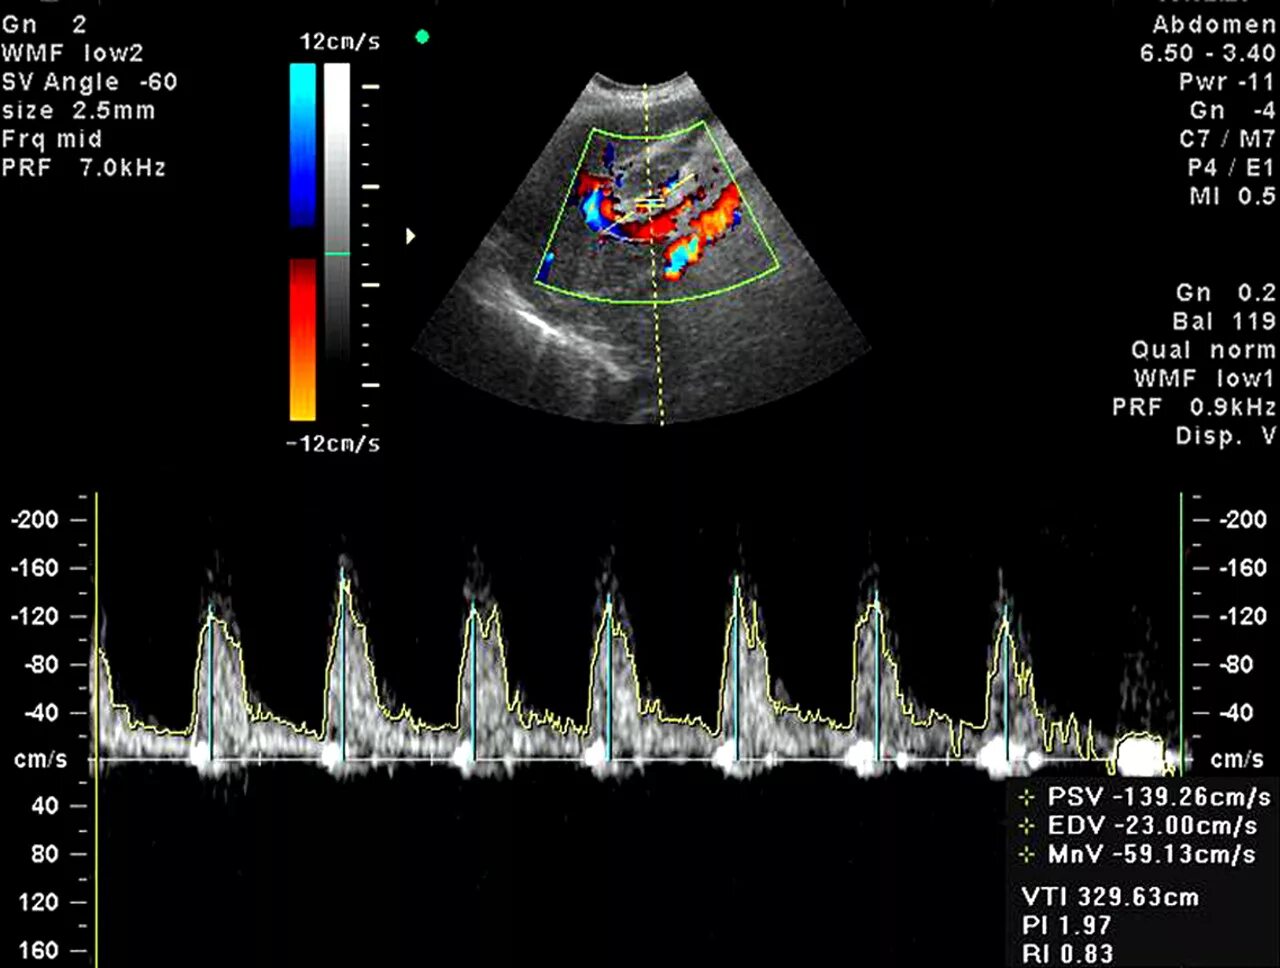

Допплер для беременных для чего